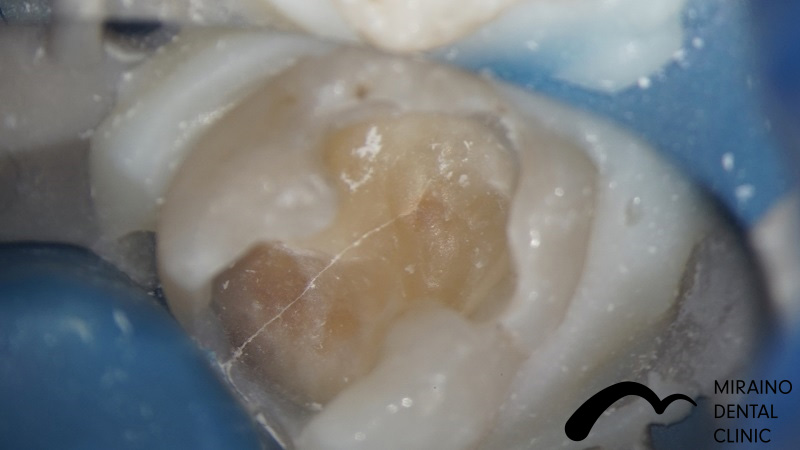

Case2

| 施術名 | 詰め物・メタルフリーインレー |

| 施術の概要 | 定期検診の際に、5年前以上に治療した銀歯に伱間があることを衛生士が見つけました。 沁みる、噛むと痛いといった症状はありませんでしたが、 次回再発した際は神経を取らないといけなくなる可能性が高いため、 なるべく再発しにくい歯科治療を希望され、メタルフリーインレーによる修復治療を行いました。 |

クリックして詳細を表示

| 施術の内容 | 銀歯は歯より硬すぎる、歯を腐食させる作用があることから約5年で再発すると言われています。 ラバーダムを用いて唾液による接着不良のリスクを排除し完全に水分を排除した状態でムシ歯治療を行います。 型取りを行い、技工士によって汚れの付きにくいセラミックで形を再現している。 |

| 1歯あたりの治療費 | 1歯:50,000円 |